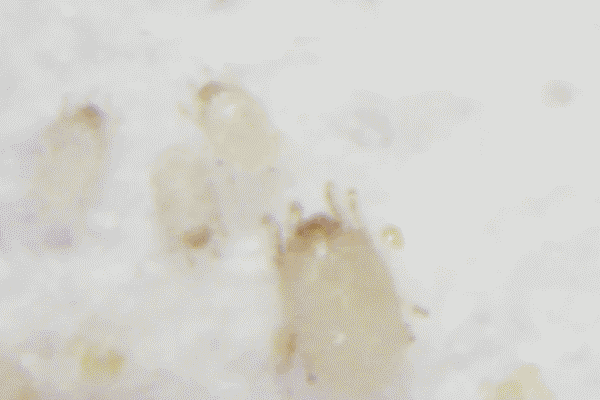

東區愛爾角膜眼表科室陳劍南醫生了解情況後,給小希做了眼前節檢查,發現(xiàn)睫毛根部不平整,還有充血,馬上拔下幾根睫毛,當場就在螨蟲顯微鏡下開始檢查,看到下面的結果,小希頓時整個人都不好了。

隻見(jiàn)一條條的蟲子在睫毛上爬呀爬。